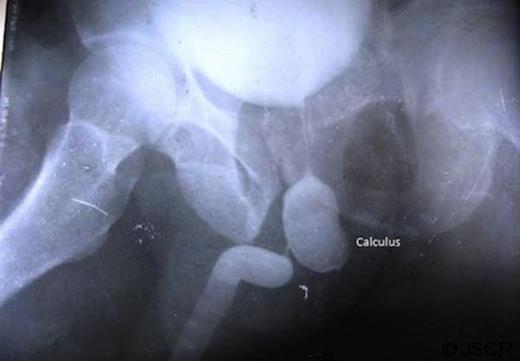

A 55 year male was admitted to our institution with complaints of pain and swelling in perineal region for 6 days and purulent discharge from the swelling for 2 days. Patient was apparently quite well 4 months prior when he noticed a progressive thinning of urinary stream along with dysuria and burning on micturition. Three months later the patient had an episode of retention of urine for which patient attended our outpatient department. A trocar suprapubic catheterisation (SPC) was performed and a 16 Fr Foley’s catheter was passed into the bladder. Patient was asymptomatic for 1 month followed by reappearance of the swelling and pain in the perineal region. On local examination there was a swelling 2 x 2 cms in size in the left perineal region with purulent discharge. Urine culture and pus culture showed growth of Klebsiella resistant to all tested antimicrobials. Patient was subjected to retrograde urethography (figure 1) and micturiting cystourethography (figure 2). Patient was diagnosed as a case of urethral calculus with urethral stricture and was posted for urethral calculus removal with urethroplasty. The calculus of 30mm x 20mm x15mm (figure 3) was extracted successfully and end to end urethroplasty was performed.